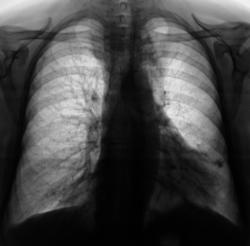

1. Загрудинный зоб

2. Опухоль средостенья

3. Сосудистая аневризма

Зоб?

вероятнее всего -зоб, диф. ряд приведен выше

Зоб.